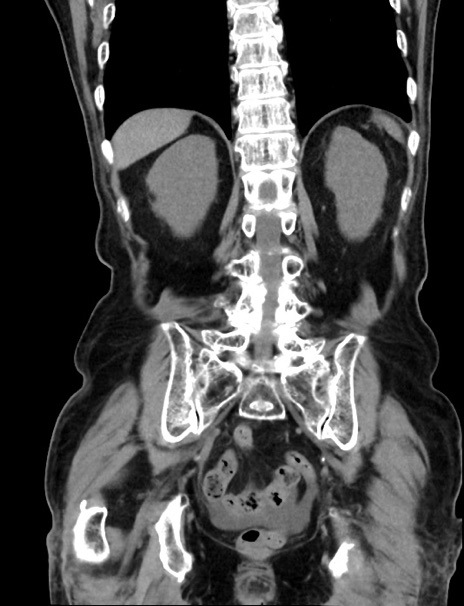

症例33(冠状断像)

【症例】70歳代 女性

【主訴】心窩部痛

【現病歴】延髄病変の精査・加療にて神経内科入院中。本日より心窩部痛あり。

【身体所見】右下腹部を中心に圧痛と反跳痛あり。

【データ】WBC 10900、CRP 0.02